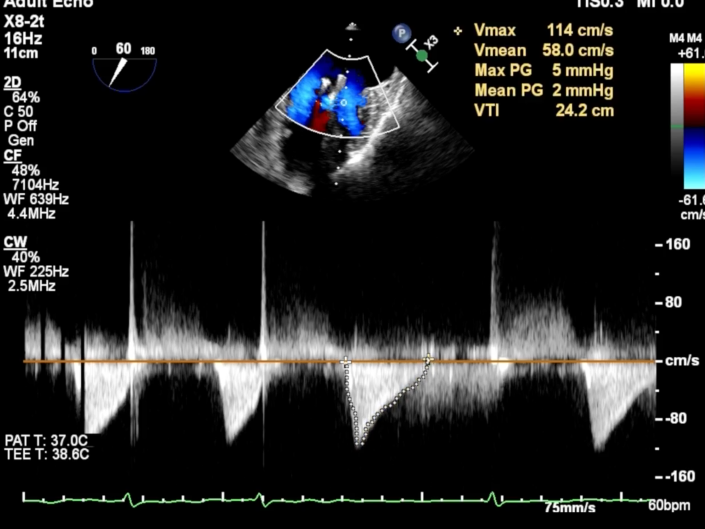

房颤,瓣环扩大的房性二尖瓣反流,反流主要集中在二区,二区后叶部分脱垂,后叶的长度16mm,前叶的长度是37mm。房间隔整体的条件可,从瓣环到拟定的卵圆窝顶部高度大概是41mm。

二尖瓣2区

二尖瓣2区color

为进一步优化效果,团队在第一枚夹子外侧以“side by side”方式植入第二枚长窄夹,最终使二尖瓣反流降至微量水平,平均跨瓣压差维持在约2mmHg。